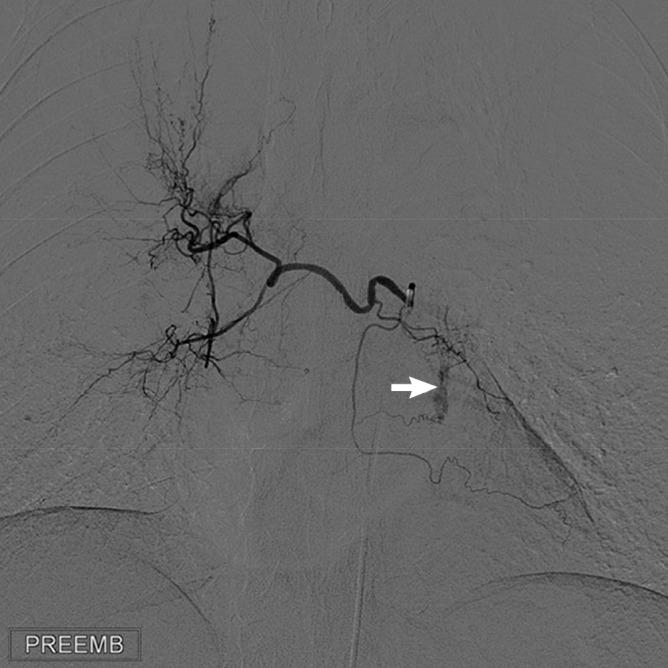

Management of cryptogenic massive hemoptysis is difficult, and conservative treatment may be inadequate to stop the hemorrhage. Surgery is not a reasonable option because there is no underlying identifiable pathology. This study aimed to investigate the radiologic findings and bronchial artery embolization outcomes in cryptogenic hemoptysis, and to compare the results with non-cryptogenic hemoptysis. We evaluated 26 patients with cryptogenic hemoptysis and 152 patients with non-cryptogenic hemoptysis. A comparison of the bronchial artery abnormalities between the cryptogenic and non-cryptogenic hemoptysis groups showed that only extravasation was more statistically significant in the cryptogenic hemoptysis group than in the non-cryptogenic hemoptysis group, while the other bronchial artery abnormalities, such as bronchial artery dilatation, hypervascularity, and bronchial-to-pulmonary shunting, showed no significant difference between groups. Involvement of the non-bronchial systemic artery was significantly greater in the non-cryptogenic hemoptysis group than in the cryptogenic hemoptysis group. While 69.2% of patients with cryptogenic hemoptysis also had hypervascularity in the contralateral bronchial arteries and/or ipsilateral bronchial artery branches other than the bleeding lobar branches, this finding was not detected in non-cryptogenic hemoptysis. Embolization was performed on all patients using polyvinyl alcohol particles of 355-500 µm. Hemoptysis ceased in all patients immediately after embolization. While recurrence of hemoptysis showed no statistically significant difference between the cryptogenic and non-cryptogenic hemoptysis groups, it was mild in cryptogenic hemoptysis in contrast to mostly severe in non-cryptogenic hemoptysis. Transarterial embolization is a safe and effective technique to manage cryptogenic hemoptysis.

隐匿性大量咯血的治疗颇具难度,保守治疗可能不足以止血。由于不存在潜在的可识别病理状况,手术并非合理选择。本研究旨在调查隐匿性咯血的放射学表现及支气管动脉栓塞术的疗效,并将结果与非隐匿性咯血进行比较。我们评估了26例隐匿性咯血患者和152例非隐匿性咯血患者。隐匿性咯血组与非隐匿性咯血组支气管动脉异常情况的比较显示,仅造影剂外渗在隐匿性咯血组比非隐匿性咯血组在统计学上更显著,而其他支气管动脉异常,如支气管动脉扩张、血管增多和支气管肺分流,两组间无显著差异。非支气管性体动脉受累在非隐匿性咯血组比隐匿性咯血组显著更常见。虽然69.2%的隐匿性咯血患者在对侧支气管动脉和/或除出血肺叶分支外的同侧支气管动脉分支中也存在血管增多,但在非隐匿性咯血中未发现这一表现。所有患者均使用355 - 500 µm的聚乙烯醇颗粒进行栓塞。栓塞后所有患者咯血立即停止。虽然咯血复发在隐匿性咯血组和非隐匿性咯血组之间无统计学显著差异,但隐匿性咯血的复发较轻,而非隐匿性咯血的复发大多较严重。经动脉栓塞术是治疗隐匿性咯血的一种安全有效的技术。